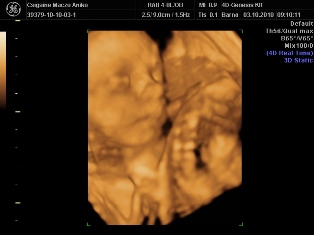

4D: a legtobb konyv azert az ellen van, hogy az anyuka az elso bevasarlokozponti 4Dszalonba beterjen kepeket csinaltatni, mintha pedikuroshoz menne... Mert azert annyira nem tutti, hogy egyaltalan nem art a babaknak (persze az orvosilag indokoltaknal tuttira nagyobb az elonyuk, mint a kockazatuk). Es tenyleg a terhesseg kozepetol az ikrek mar nehezen latszanak, ugyhogy koran erdemes elmenni, ha mar megy valaki. Ami helyet en nagyon tudok ajanlani, az az Istenhegyi genklinika. Ott kombinalt teszttel, mindennel egyutt csinalnak 4D-t is; kap az ember DVD-t is, kepeket is, es rendkivul alaposak es kedvesek az orvosok, es mindent nagyon-nagyon jol elmagyaraznak. Raszanjak az emberre rendesen az idot, nem az az erzesed, hogy na, mikor mesz mar es jon a kovetkezo. Egyszer kepzeljetek, olyan is volt, hogy amikor meghalt a magzatom (11. het korul), es elmentem vizsgalatra, nem is fogadtak el penzt erte... AMugyis arban is szerintem nagyon korrektek (Becsben mult heten 250 eurot kertek egy reszletes UH-ert; es semmi kepet vagy DVD-t nem adtak ;-(.). Es ha osszekombinalod a kombinalt teszttel vagy valamivel, nem tetted ki a babat felesleges plusz UH-nak.